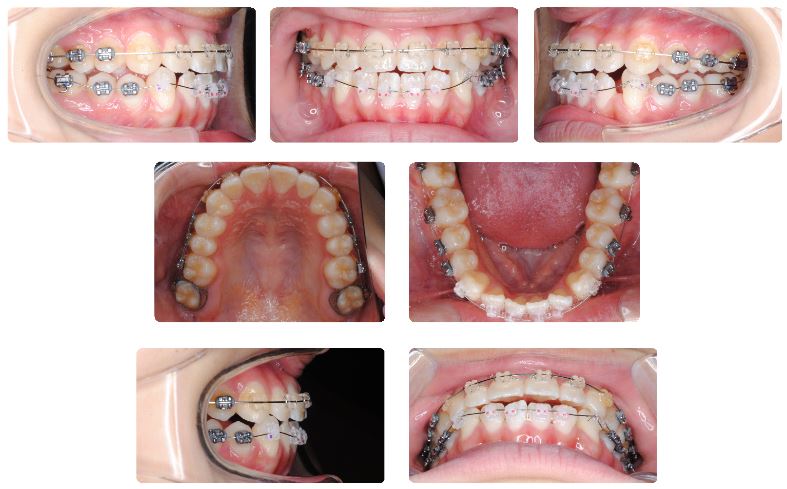

2症例目は10代後半の女性です。

上顎の治療を先行しています。現在上顎左側の小臼歯のねじれを改善している最中です。

上顎の小臼歯のねじれが改善されてワイヤーもしっかりとしたものに交換した時点で、下顎にカリエールモーションを装着しました。

カリエールモーション装着から3か月後の状態です。

下顎前歯にスペースが認められるようになりました。また下顎前歯も内側に入ってきています。

カリエールモーションの使用期間は4か月でした。

カリエールモーションを外してマルチブラケット装置を装着した直後の状態です。

下顎にマルチブラケット装置を装着後4か月後の状態です。

現在ゴムメタルという素材のワイヤーで治療継続中です。